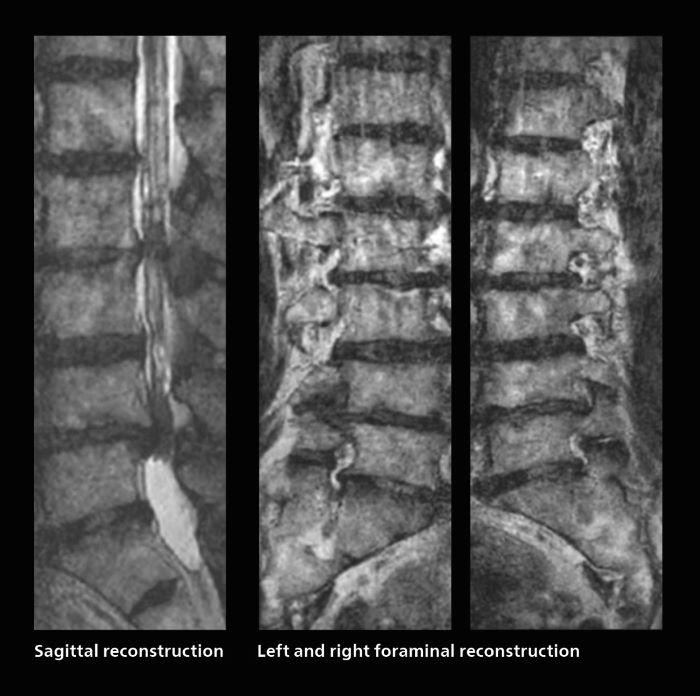

Many patients who must undergo a lumbar spine examination suffer from back pain. For these patients it is difficult to maintain the imaging position long enough to successfully complete the examination. “In such cases, using SmartSpeed allows us to perform volume imaging, so that we acquire only one high resolution 3D sequence in a short time and then reconstruct the other orientations from that,” Dr. Katahira says. “This is highly advantageous because the patient needs only endure a short exam time, whereas before it was necessary to acquire a larger number of sequences in total. We have seen that the shorter time has allowed us to scan patients who previously could not finish the exam. This is a great advantage.”

With SmartSpeed, Kumamoto Chuo Hospital also has the ability to use EPI diffusion-weighted imaging (EPICS-DWI) with Compressed SENSE, which is an important step forward according to Dr. Katahira. “Before, our EPI diffusion was performed using SENSE, but now with Compressed SENSE it is possible to obtain very clear images,” he says. He also describes the benefit of being able to perform 3D diffusion-weighted imaging. “Previously, we only had DWI images in one direction to make a diagnosis. Now, we can do something that was not possible before: performing a DWI volume acquisition so that multiplanar reconstruction can be used, allowing us to look at scan results from all directions to make the diagnosis,” Dr. Katahira says. “What used to be a diagnosis based on just cross-sectional images, can now be based on a volume image. This is a dramatic improvement for us, because it is now possible to look at slices in various cross section directions. For example, the presence or absence of venous invasion is very important in rectal cancer patients, because venous invasion can cause metastasis in the future. The ability to reconstruct images according to the direction of the blood vessels, allows us to see venous infiltration more realistically, which is a world of difference from what we were used to.”

In this patient MRI was done to help in diagnosing the depth of invasion. Performed on Elition X.